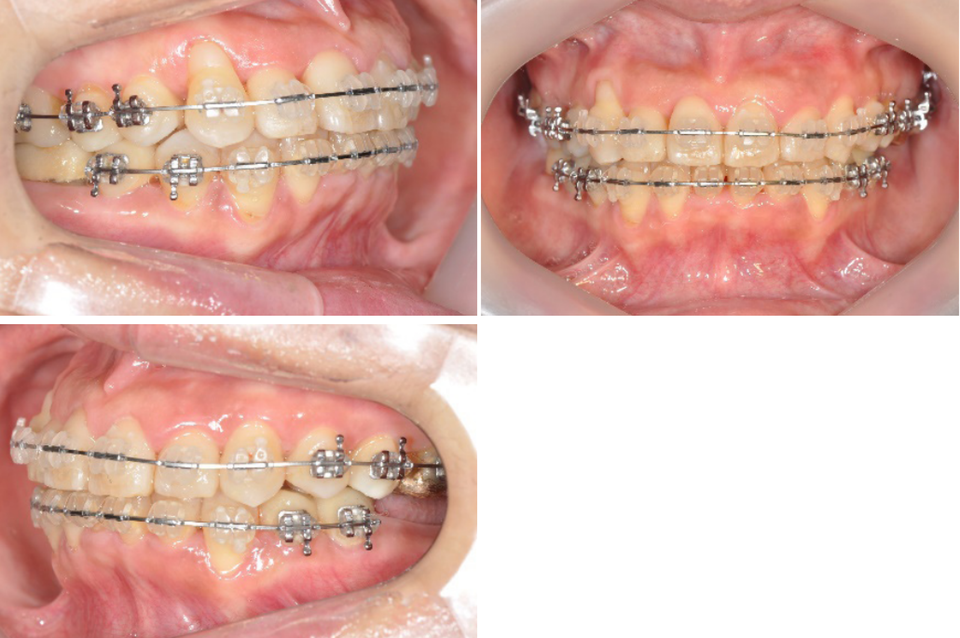

하악임플란트상부보철물에 tube를 부착하되 tube slot에 각형호선이 가급적 passive 하게 들어가도록 보철물의 모양과 tube 부착위치를 조절하였습니다. 계획된 후방이동량만큼 임플란트 보철물과 전방 자연치간의 space를 형성하여 전방치열을 후방견인하였습니다.

마무리된 교합은 초진시에 동일하게 양측 Class 1 교합으로 마무리하였으며 측모두 부방사선 사진에서 보듯 교정중 발생했던 전치의 flare가 개선되었습니다.